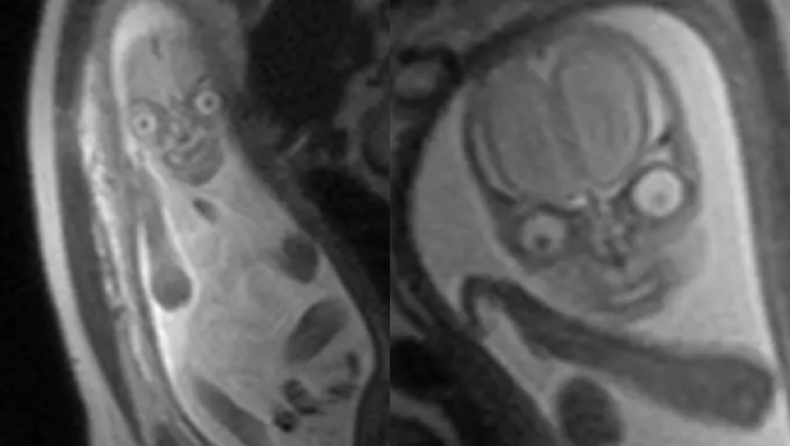

Η τρομοκρατική απεικόνιση ενός μωρού στην μαγνητική τομογραφία

Η απεικόνιση μαγνητικού συντονισμού, κοινώς γνωστή ως μαγνητική τομογραφία, έχει φέρει επανάσταση στην ιατρική διάγνωση, επιτρέποντας στους γιατρούς να απεικονίζουν τις εσωτερικές δομές με αξιοσημείωτη λεπτομέρεια. Όταν εφαρμόζεται στην προγεννητική απεικόνιση, η μαγνητική τομογραφία παρέχει μια μη επεμβατική μέθοδο παρατήρησης της ανάπτυξης ενός εμβρύου μέσα στη μήτρα της μητέρας. Η τεχνολογία χρησιμοποιεί ένα ισχυρό μαγνητικό πεδίο και ραδιοκύματα για τη δημιουργία εικόνων διατομής, προσφέροντας ένα παράθυρο στα περίπλοκα στάδια της ανάπτυξης του εμβρύου.

The real reason they discourage MRIs during pregnancy is because then people would realise they’re incubating nightmare demons and would be rightfully terrified pic.twitter.com/55zEeOofsP

Από την άλλη πλευρά, υπάρχουν εκείνοι που βιώνουν ένα αίσθημα τρόμου βλέποντας αυτές τις εικόνες. Η θέα ενός πλήρως σχηματισμένου μωρού μέσα στη μήτρα μπορεί να προκαλέσει σύγχυση σε ορισμένα άτομα, προκαλώντας ένα μείγμα γοητείας και ανησυχίας. Η αντίδραση αυτή δεν είναι ασυνήθιστη, καθώς η ιδέα της απεικόνισης μιας αναπτυσσόμενης ζωής με τέτοια λεπτομέρεια μπορεί να προκαλέσει τις αντιλήψεις μας και να μας φέρει αντιμέτωπους με την εντυπωσιακή αλλά και μυστηριώδη διαδικασία της ανθρώπινης αναπαραγωγής.